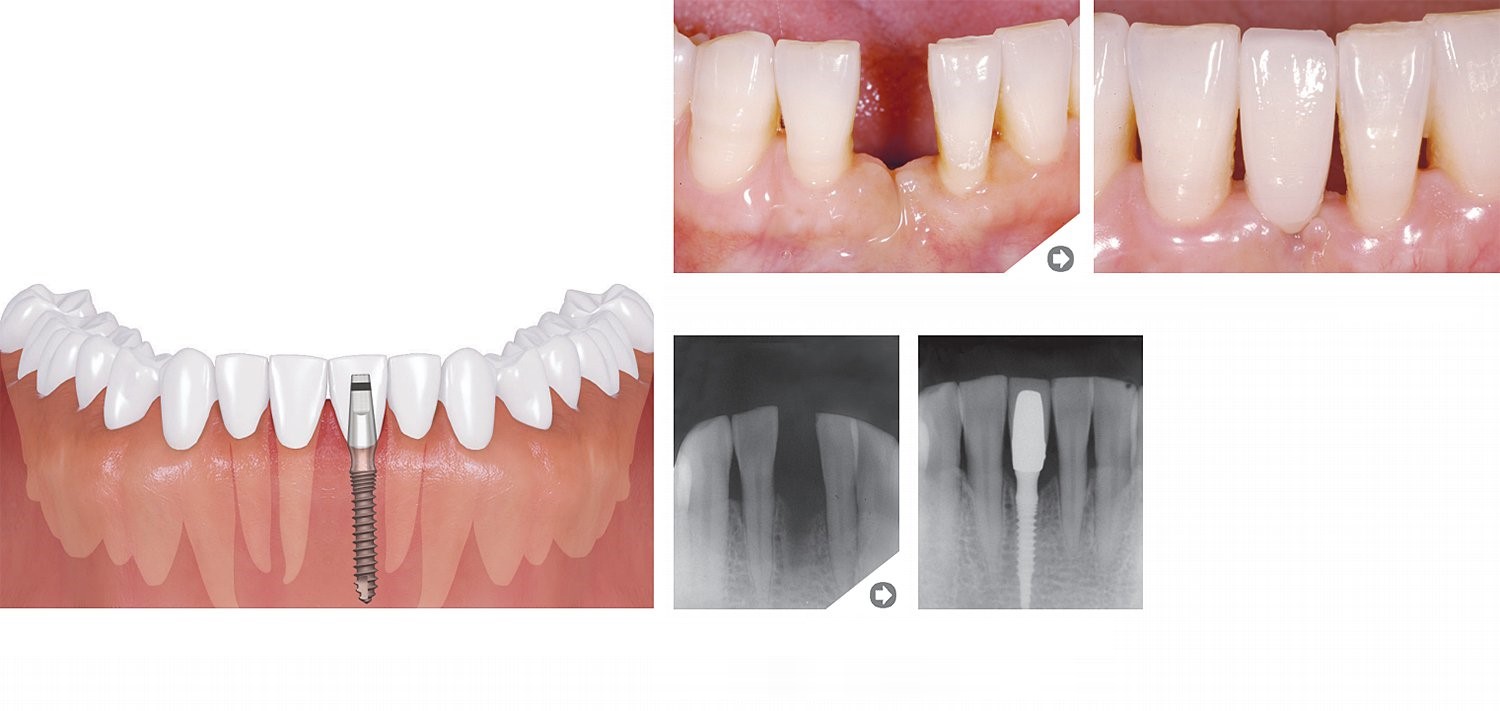

Trūkst viena zoba

Priekšējais zobs